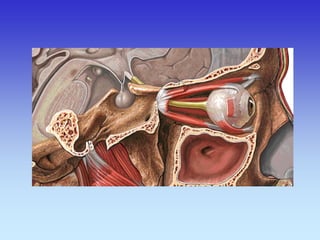

ORBITE

PRIJELOM DNA ORBITE

KORONARNI SLOJ

CT ORBITA